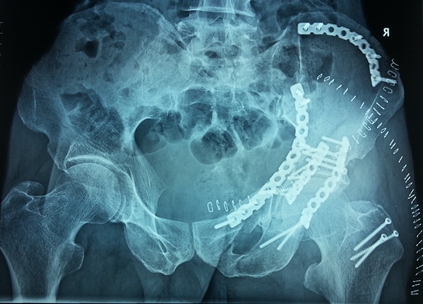

燕化医院开展手术治疗四肢、骨盆骨折患者取得了良好的效果。股骨颈骨折一般以全髋关节置换(THA)和半髋关节置换为主;而对于股骨转子间骨折的外科治疗多采用内固定手术,包括锁定钢板;动力髋系统即DHS、PFN(A)。具有创伤小(微创)、内固定牢固、术后恢复快便于提早下地活动等优点。肱骨、尺桡骨、股骨干、胫骨干的骨折主要采用带锁髓内钉和锁定钢板治疗;复杂的骨盆骨折则采用切开复位,重建钢板治疗。

图3. 复杂的骨盆骨折术前

图4.复杂的骨盆骨折则采用切开复位,重建钢板治疗